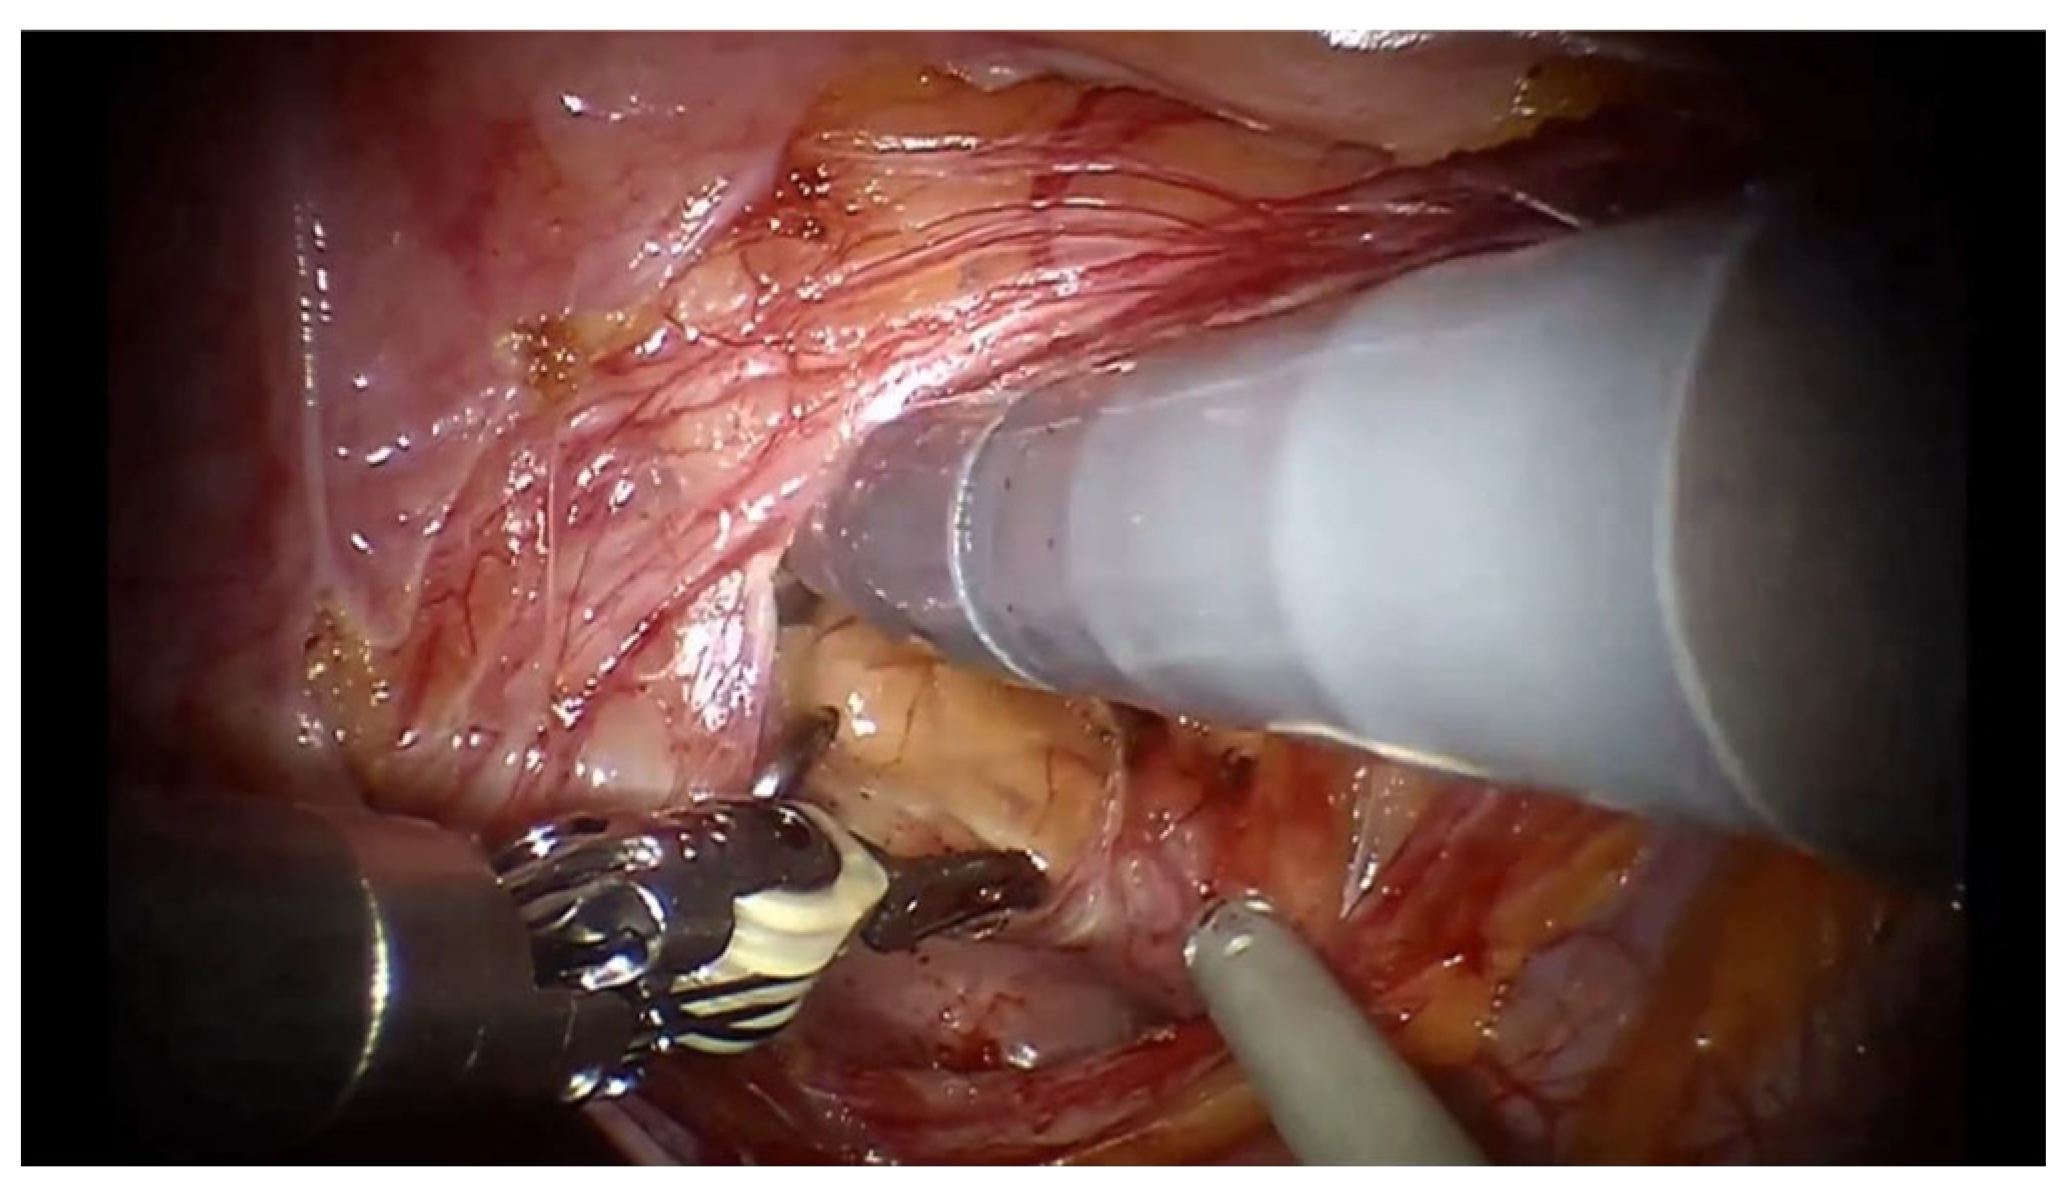

Minimally Invasive Guidewire-Aided Bladder Diverticulectomy with or Without Other Prostatic Intervention: Step by Step Description of the Procedure

3. Surgical Technique